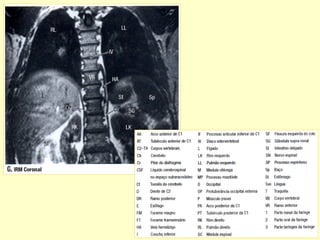

Conteúdos intra-raquianos

RELAÇÕES ANATÔMICAS DA COLUNA

ANATOMIA RADIOLÓGICA CERVICAL

Anatomia radiológica